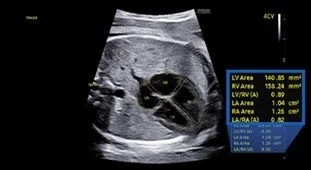

AI is transforming healthcare, as our team at CeCe’s Place knows from experience. Our Samsung V7 Ultrasound provides AI fetal heartbeat monitoring, image classification, and biometric measurements. To read more about AI’s role in North Texas healthcare, click this link.